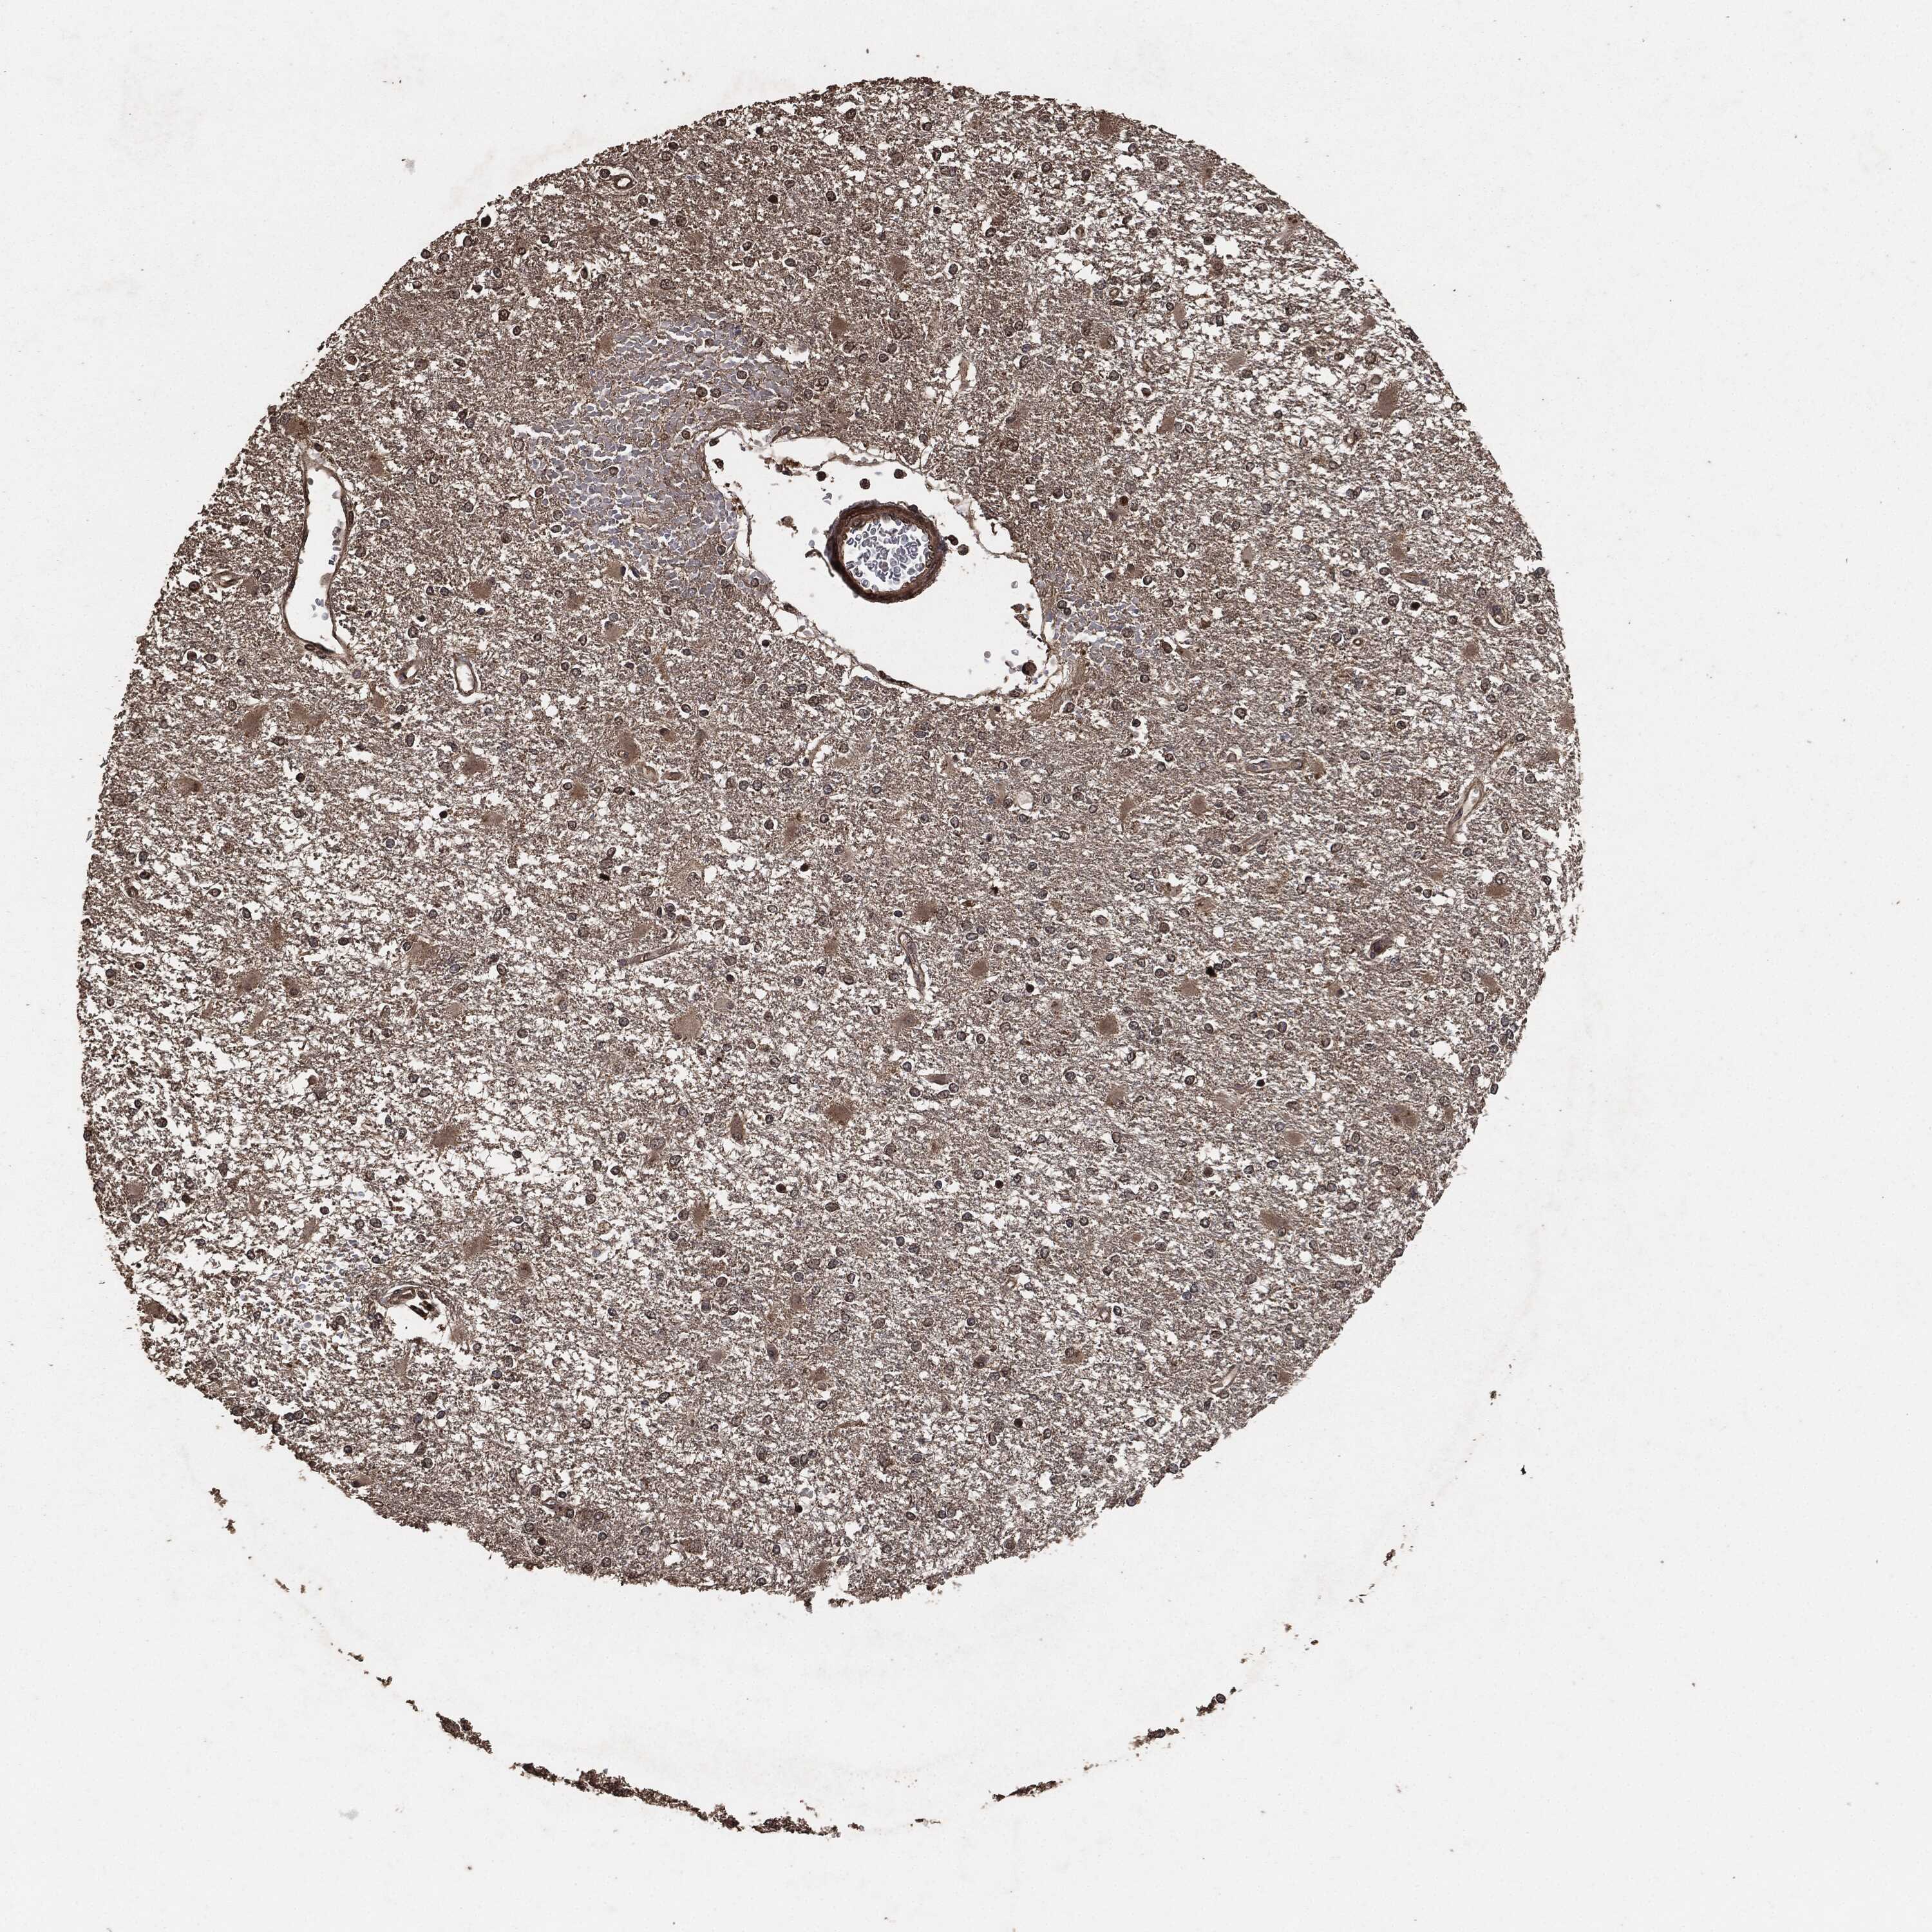

GLIOMA - Protein expressioni

A mouse-over function shows sample information and annotation data. Click on an image to view it in a full screen mode. Samples can be filtered based on level of antibody staining by selecting one or several of the following categories: high, medium, low and not detected. The assay and annotation is described here.

Note that samples used for immunohistochemistry by the Human Protein Atlas do not correspond to samples in the TCGA dataset.

Antibody stainingi

Antibody staining in the annotated cell types in the current human tissue is reported as not detected, low, medium, or high, based on conventional immunohistochemistry profiling in selected tissues. This score is based on the combination of the staining intensity and fraction of stained cells.

Each image is clickable and will lead to virtual microscopy that enables deeper exploration of all samples and also displays staining intensity scores, fraction scores and subcellular localization as well as patient and tissue information for each sample.

Antibody HPA064427

Antibody HPA075510

Antibody CAB021903

Staining

High

Medium

Low

Not detected

Intensity

Strong

Moderate

Weak

Negative

Quantity

>75%

75%-25%

<25%

None

Location

Nuclear

Cytoplasmic/membranous

Cytoplasmic/membranous,nuclear

Glioma, malignant, Low grade

Glioma, malignant, High grade